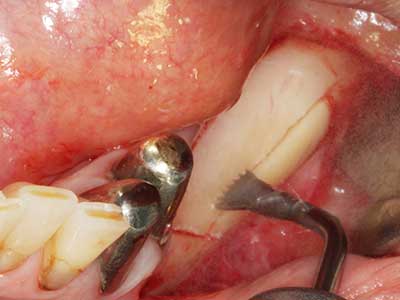

Indication: Preparation near nerves

Indication: Apical resection

When surgical procedures are performed on bone in the immediate vicinity of sensitive structures such as blood vessels or nerves, rotary instruments pose a significant risk of iatrogenic injury. Piezoelectric devices can be helpful for preparation of bone covers and removal of hard tissue close to nerves, particularly for exposure of nerves after iatrogenic injury but also during nerve lateralization for resective and reconstructive procedures or implant placement (Fig. 17-20). Light contact between the piezotip and the nerve does not generally result in damage but proceeding incautiously with saw-like motions or attachments where a residual bone substrate remains may cause temporary or even permanent nerve damage. However, the risk of damage is considered to be substantially lower than when using saws or milling instruments (Pereira, Gealh et al. 2014).